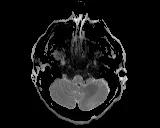

Conventional Deep Resolve

Deep Resolve is our AI-powered image reconstruction technology for MRI

• Enabling faster acquisitions, increased clinical productivity and better patient experience

• Increased image quality and resolution

• Reduced energy consumption per acquisition 2x